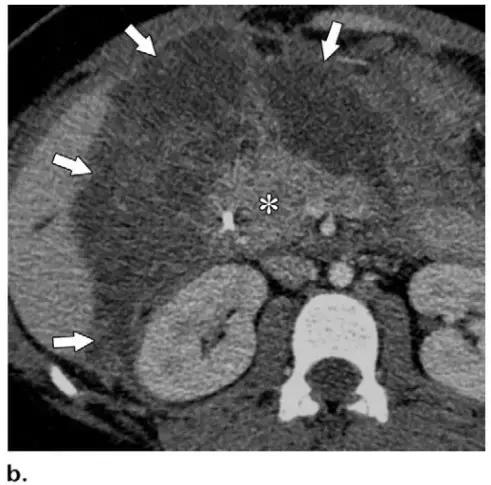

胰周型:表现为胰腺强化正常,而胰周坏死,坏死物可包括不等量的液体和和非液性成分,约占坏死性胰腺炎的 20%(图 3b)。

图 3 坏死性胰腺炎亚型在增强轴位 CT 的表现。a 胰腺和胰周同时受累的 58 岁女性患者,胰体无强化(*),正常强化的胰尾(黑箭头),小网膜囊内 ANC(白箭头)。b 仅胰周受累的 18 岁男性患者,可见一周为大片不均质密度(箭头),和 ANC 相符。胰腺实质密度正常(*)。c 仅胰腺实质受累的 33 岁男性患者,可见大片局限无强化的胰腺实质和脂肪密度(*),诊断为 WON。仅周边可见少量残余强化的胰腺实质(箭头)